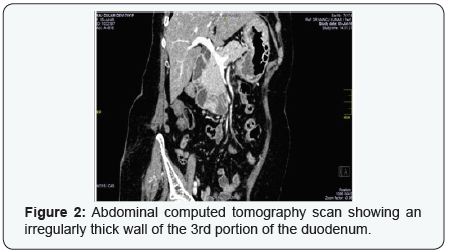

A 70-year-old woman was admitted with a complaint of vomiting after intake of meal. Upper gastrointestinal endoscopy revealed large nodular growth in 3rd and 4th part of duodenum (Figure 1), and the endoscopic biopsy showed an early invassive adenocarcinoma of the duodenum. Computed tomography of the abdomen revealed (25*20) mm heterogenously enhancing endophytic mass at D2 -D3 junction noted from inferior wall of duodenum causing partial obstruction (Figure 2). Laparotomy did not reveal direct invasion into the pancreas, liver, peritoneal dissemination, ascitis, or distant metastasis. There was a tumor involving 3rd part of duodenum detected after duodenotomy in 3rd part of duodenum. After that, surgeon decided to avoid a duodeno -pancreatectomy and opted segmental resection of the duodenum (SRD) with a end to end anastomosis. A growth noted about 2 cm away from ampilla of vater, 1 cm tumor free proximal margin dissected and segmental resection of the growth in D3 part of duodenum done, with end to end anastomosis. Histological examination showed papillary adenocarcinoma of the third part of the duodenum with margin free from tumor .Thus definitive diagnosis was primary adenocarcinoma of the 3rd portion of the duodenum, exact site was detected intraoperatively. Her postoperative course was uneventful, followed at 2 week, 1 month, 3 month; 6 month .She is without any sign of recurrence 6 month later.